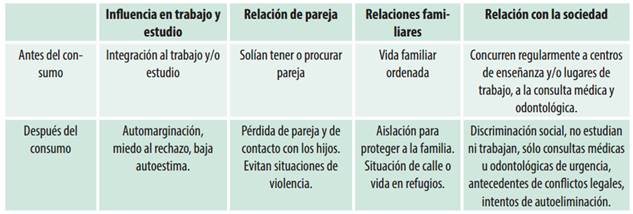

Considerando la categoría “relación con el entorno” se encontraron los siguientes resultados sobre influencia en trabajo y estudio, relación de pareja, relaciones familiares y con la sociedad antes y después de la situación de consumo (cuadro 4).

Sobre la relación con el entorno antes del consumo problemático eran individuos en actividad escolar o laboral, con pareja o en procura de tenerla, que concurrían regularmente a centros de enseñanza y/o lugares de trabajo, a la consulta médica y odontológica. Después del consumo abusivo, manifestaron situaciones de automarginación por miedo al rechazo, baja autoestima, pérdida de pareja o contacto con los hijos, si los tuvieran, para evitar situaciones de violencia. También expresaron la opción de aislamiento de la familia para protegerla, situación de calle o vida en refugios, además de desistir de la asistencia a la consulta médica u odontológica al sentirse marginados o discriminados, con intentos de autoeliminación y conflictos legales que los pueden conducir a la privación de libertad.